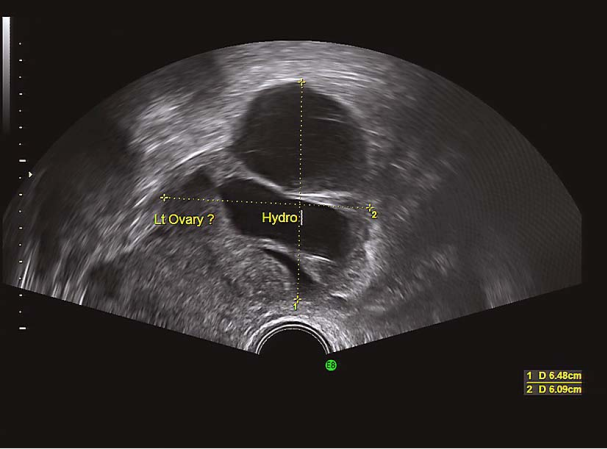

卵泡生长发育监测(排卵前期) 输卵管积水超声表现 输卵管积水超声表现

(2)激素测定:排卵障碍和年龄≥35岁女性均应行基础内分泌测定,于月经周期第2~4日测定FSH、LH、E2、T、PL基础水平。排卵期LH测定有助于预测排卵时间,黄体期P测定有助于提示有无排卵、评估黄体功能。